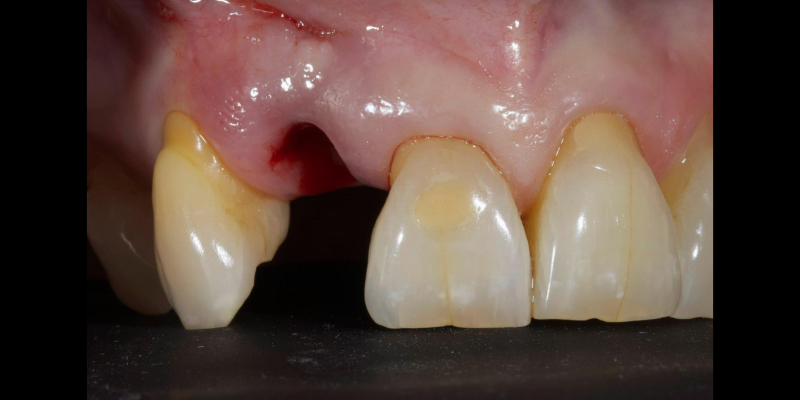

Take Arthur, a 76-year-old man who presented with a vertical root fracture of his upper left central incisor. His medical conditions precluded his request for an implant, so he agreed to the proposal for an adhesive bridge instead.

The tooth was extracted and for four months the pontic site was conditioned with a removable Essix-type of denture (Fig. 1).

An e.max (lithium disilicate), one-wing (adjacent central being the retainer) bridge was placed, which resulted in an acceptable outcome (Figs. 2-4) that was more timely and at a lower financial and biological cost to the patient than the implant Arthur initially thought he wanted.